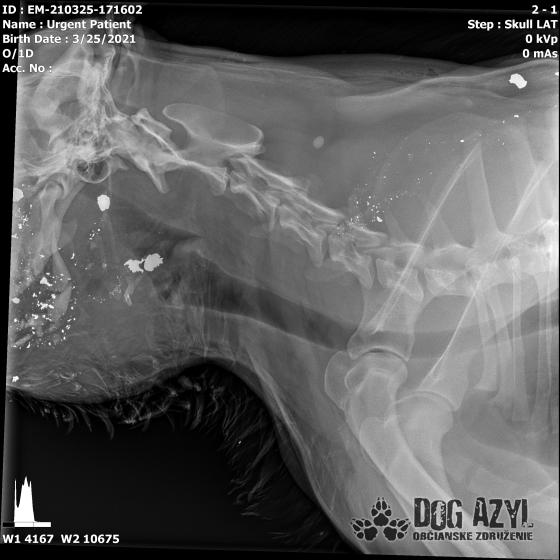

Ona ležala na ľavo, on na pravo od zavesenej šunky, ktorá mala zrejme slúžiť ako návnada, aby sa terče nehýbali.. Uprostred ničoho, bez svedkov, bez dôkazov... Pár kvapiek krvi na ceste.. Ona to schytala jedinou ranou do srdca.. On má roztrieštenú sánku, schytal to do hlavy..

/Strašne to chcem dopísať tak, aby to bolo čitateľné a pochopiteľné, ale celá sa klepem od zlosti a nevidím cez slzy.../ Lebo Ona už meno nikdy nebude mať.. On dostal meno Baris a bojuje o život!!! Má dolámanú sánku a je v šoku!!! Dostal prvú pomoc, analgetiká a priorita bola znížiť jeho teplotu z 41,4°C!!!

Ústami nevie pohnúť, jazyk si nevie ovládať a tak sa sám nedokáže schladiť ani napiť. Podľa RTG sú srdiečko a pľúca v poriadku, ale vôbec nemá vyhraté!!! Niekto chcel Barisa zlikvidovať, ale my za neho budeme bojovať do posledného dychu!!! Zajtra bude prevezený na veterinárnu kliniku Sibra centrum, kde ho čaká team špecialistov z oblasti chirurgie, neurológie a ortopédie. Ak je čo i len najmenšia nádej, že Baris bude môcť žiť, tak BARIS BUDE ŽIŤ!!!